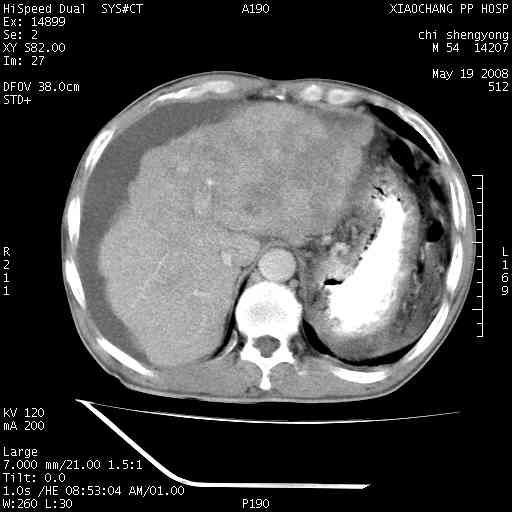

以下是引用zjzjr在2008-5-21 10:52:00的发言:[br]肝左叶巨块型肝癌伴门静脉左支瘤栓形成.肝硬化、腹水,胃底静脉曲张,脾术后改变。

以下是引用随光逐影在2008-5-21 16:20:00的发言:[br]1)肝左叶肝癌伴门静脉左支瘤栓形成,腹膜后淋巴结转移。2)肝硬化、腹水、胃底静脉曲张。3)胆囊炎。4)脾脏缺如,为切除术后所致。